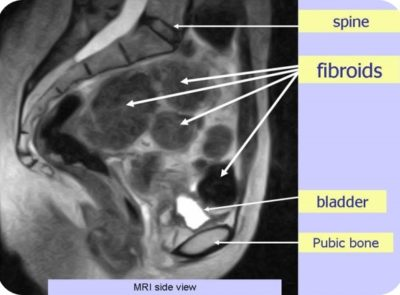

FIBROIDS

- Fibroids are benign tumours which can develop in the wall of the uterus.

- Classified according to their location in the uterus.

- sub serous – fibroids form on the outer wall of the uterus called serosa.

- Intramural – fibroids appear within the muscular wall of uterus called the myometrium

- Submucosal – fibroids project partially or completely into the uterine cavity

- MRI